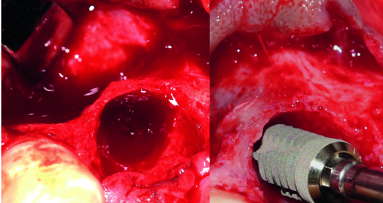

After nasal intubation and local anesthesia the bridge in the lower was removed and the remaining teeth despite from 18 and 19 as mentioned before (Figs. 3 & 4). After full flap preparation with crestal incision, releasing incisions and exposure of the mental nerve exit, the volume of the severe bone loss was revealed as well as the minor soft tissue conditions due to inflammatory tissue proliferation (Figs. 5 & 6). The success of 3-D bone augmentation is bonded to primary wound closure and tensionless flap adaptation. Thus, the periosteum is dissected with a scissor from the epi periostal connective tissue before augmentation procedures to reduce bleeding and guarantee a flap flexibility without compromising soft tissue and nutritive blood vessels.

For bone augmentation a bone block was harvested via ultrasonic surgery from the retromolar region distal from 32 of the right mandible (Piezotome II, Acteon France).

This bone block was devided into two halfs. One was used for two “bone shields” to create a mold for the grafting material, one was particulated with a bone mill and mixed with defect blood and a beta-TCP (Nanobone, Artoss GmbH, Rostock, Germany). The bone blocks were fixed with two osteosynthesis screws (Fig. 7) and the mixture of autologenous bone plus beta-TCP in mixing ratio 50 : 50 was used to fill the gaps and increase the rigde width and height. To increase the bone augmentation material volume an allograft block (Puros, Zimmer Dental) was particulated and added to the mixture. Before placing the material a non resorbable titanium-reinforced membrane (Cytoplast Ti-250, Sybron Implant Solutions) was adapted lingually and folded to shape the augmentation complex according to the new and desired crest volume (Fig. 8).

The well vascularized bone was used to insert 4 dental implants (4 x 3.75 x 13 BEGO Semados, BEGO, Germany) for a later bar-retained denture, the healing time is estimated with 8 weeks (Fig. 13) and was not completed before publication, here my apologies to that.